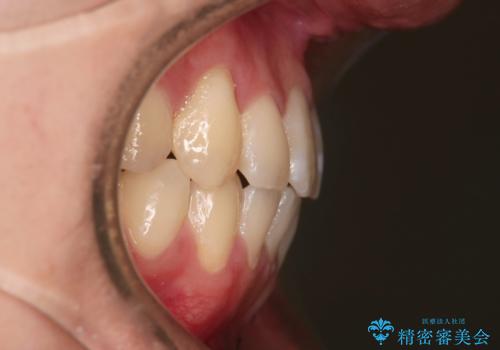

歯の移動にオープンコイルとMI(歯肉に埋入するネジ)を用いました。

非抜歯矯正だったこともあり、1年半以内という短い期間で矯正を終了することができました。

気にされていた八重歯とがたつきが綺麗に改善されました。